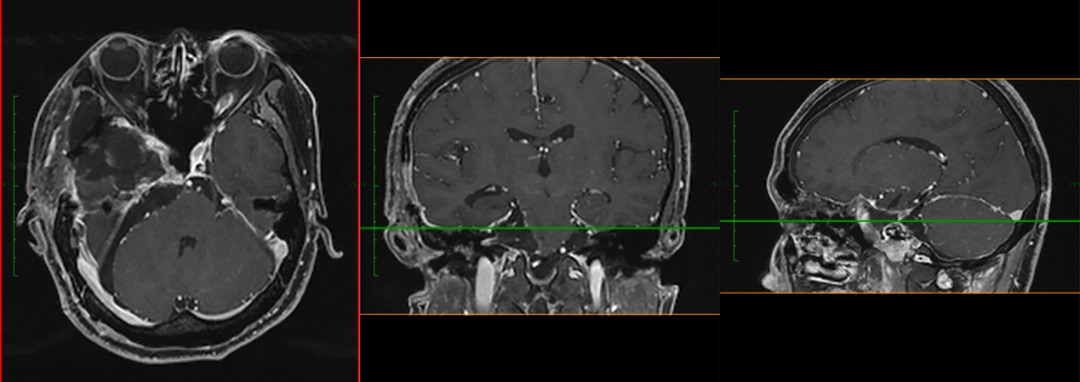

神经外科濮春华主任医师和团队在显微镜下娴熟地操作,在麻醉医师、手术室护士及输血科的密切配合下,11个小时后, “盘踞”在中颅窝处的肿瘤被近全切除,一个月后,残余在后颅窝的肿瘤也顺利被“摘除”,两次手术总计20余小时,最终获得成功。术后病理证实软骨及黏液基质的肿瘤,符合软骨肉瘤 II级。

病理结果回报后,神经外科第一时间邀请放疗科高云生主任协助会诊,根据术后复查MR的结果,为减少复发可能,决定为小成进行质子治疗。如今,小成恢复良好,头晕和视力下降等症状得到明显的改善,已经顺利从神经外科出院。